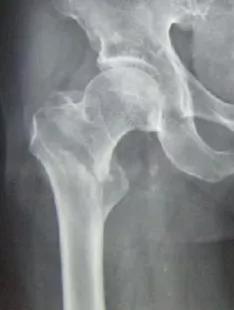

图1.右侧股骨转子间骨折(图片来源于网络)

目前,老年股骨转子间骨折隐性失血的发生机制尚未完全明确,可能与血液渗入组织间隙及溶血等因素有关。由于股骨转子间位于髋关节囊外,血运丰富,骨折后出血量较大。

另外,关节囊外骨折出血不受关节囊的限制,可沿组织间隙不断外渗,出血量较多,尤其是转子间骨折,骨折线位于血供丰富的松质骨,可引起大量出血导致围术期贫血的发生。